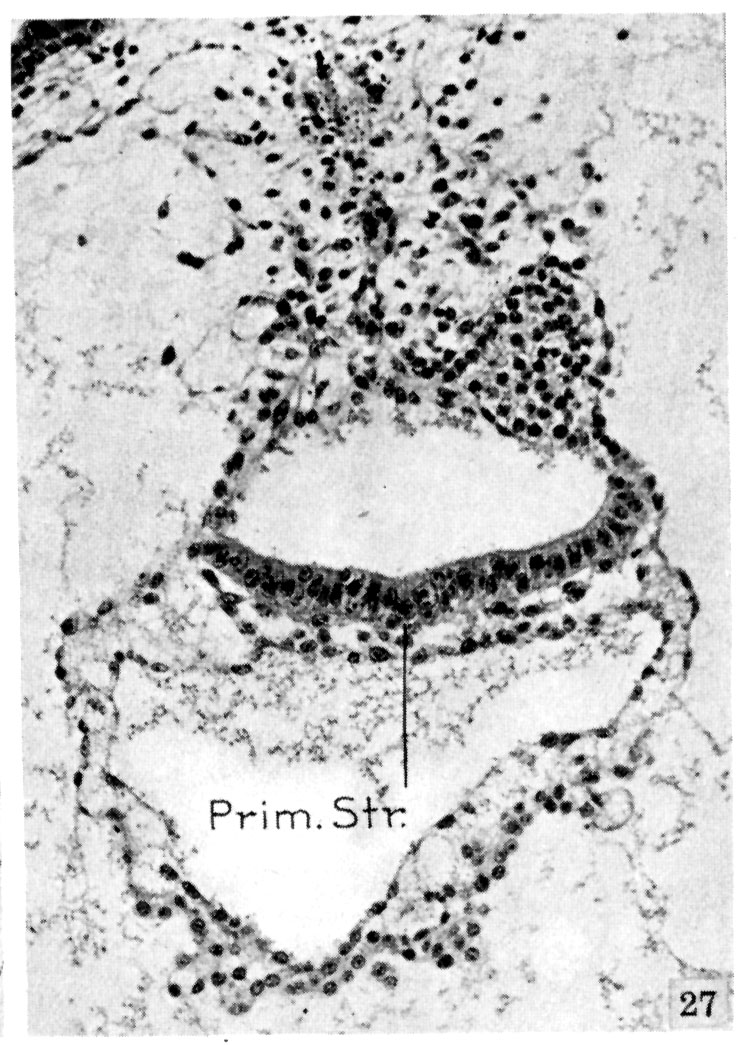

A very shallow groove is seen in the germ disk overlying the primitive streak. The clump of cells forming the distal end of the amniotic duct contains degeneration granules, and the boundaries of the cells cannot be made out. Section 405.

Keywords: amniotic duct, degeneration granules, primitive streak